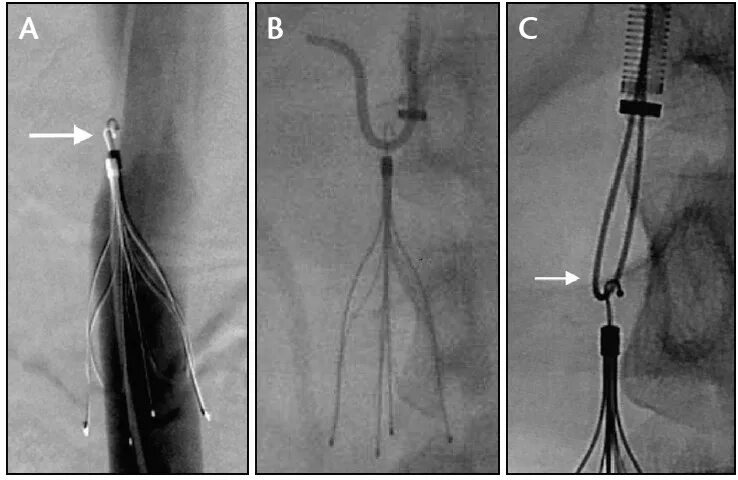

Операции при тромбозе